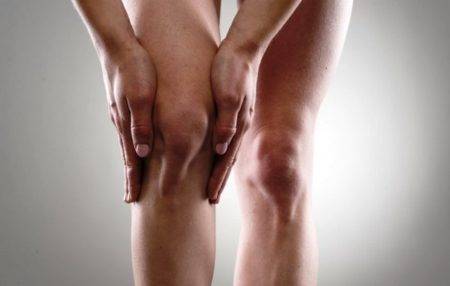

В настоящее время существуют порядка пятидесяти заболеваний коленных суставов. Все они требуют индивидуального подхода в лечении, но имеют ряд общих признаков, наличие которых должно явиться сигналом о проблемах с коленом, требующих лечения. Симптомы воспаления коленного сустава следующие:

- Разная по интенсивности боль в колене, которая может проходить и начинаться вновь.

- Краснота и отек в области колена.

- Деформация колена.

- Скованность движений после состояния длительного покоя.

- Повышение температуры тела.

- Нагноение в суставе (гнойный гонит).

Чаще всего боль резкая, возникающая после начала движения, в запущенных хронических случаях появляется отек, неприятные ощущения в области колена могут сохраняться постоянно.

Клинические симптомы воспаления коленного сустава развиваются быстро и могут включать в себя следующие проявления:

- покраснение кожных покровов вокруг сочленения костей – говорит о том, что в очаг патологии стягиваются лейкоциты и обеспечивается максимальный приток крови;

- отечность колена – происходит за счет накопления в очаге поражения лимфатической и межклеточной жидкости;

- резкая болезненность при движении (воспаление затрагивает фасции мышц и сухожилия, что затрудняет их работоспособность, на фоне отечности происходит компрессия мелких нервных окончаний;

- при пальпации может быть слышна крепитация (небольшой хруст).

При появлении этих симптомов воспаления коленного сустава необходимо срочно обратиться за медицинской помощью. С помощью рентгенографического снимка врач исключит вероятность травматического поражения костной ткани, развитие деформирующего остеоартроза.